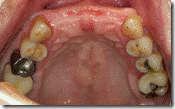

患者A先生

上顎 正面 下顎

患者B小姐

以上兩位患者口內狀況非常複雜,要制定一個好的治療計畫,

不只要考慮到患者的牙齒條件,

還要顧及患者意願、時間、金錢、評估可獲得的結果等等。

所以像這類型的Case 醫師通常在初步的溝通後會先做出一兩個不同的治療計畫,

再和患者解釋,了解患者接受程度。